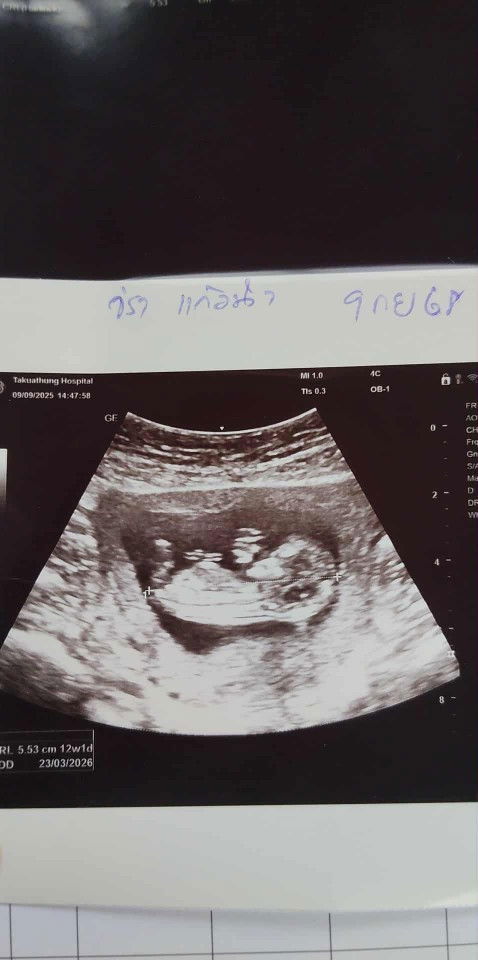

12วีค1วันค่ะ พึ่งซาวด์วันนี้เลยชัดมาก

บ้านนี้ซาวน์ตอน9w ตอนนี้14w+4แย้วค่าา ❤️